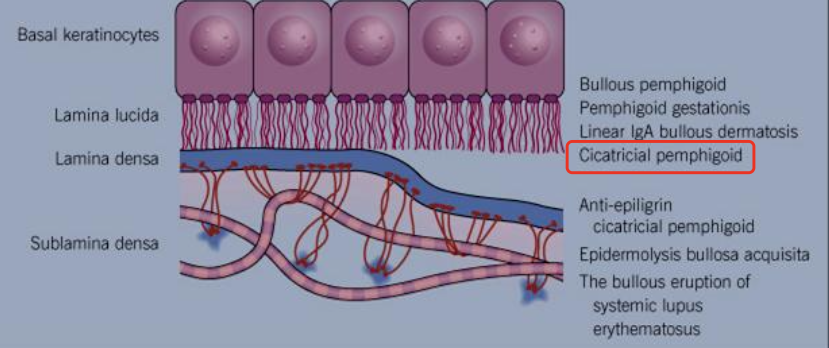

What is another name for Mucous Membrane Pemphigoid?

Cicatricial pemphigoid and Benign mucous membrane pemphigoid

What is Mucous Membrane Pemphigoid?

A chronic autoimmune disease that affects the oral mucosa, conjunctiva, genital mucosa, and skin

How could Mucous Membrane Pemphigoid heal?

With scarring (cicatricial pemphigoid)

What demographic does Mucous Membrane Pemphigoid affect?

Gender: F > M (2:1)

Age: older adults (60’s) compared to PV

Where might you find Mucous Membrane Pemphigoid?

Skin and mucosa (mouth, genital, eye)

And intraorally: gingiva (most common)

What is a unique clinical feature of Mucous Membrane Pemphigoid?

Symblepharons (fibrous scars) along the eye